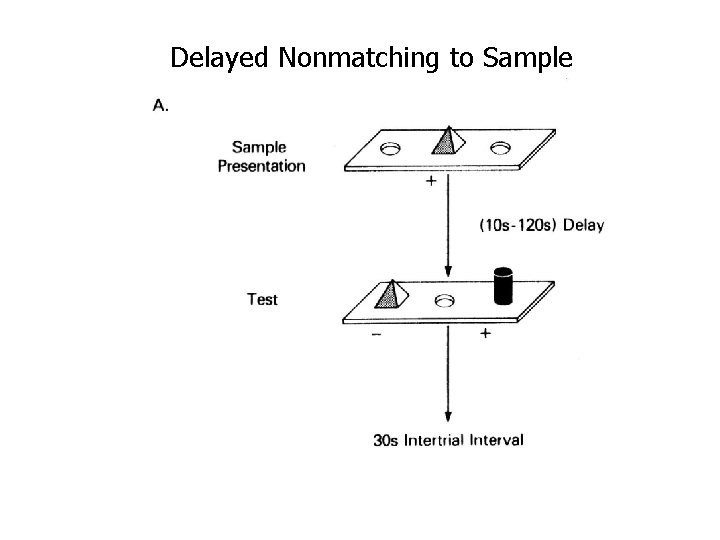

Delayed Nonmatching to Sample

Delayed Nonmatching to Sample, multiple trials, trial-unique objects